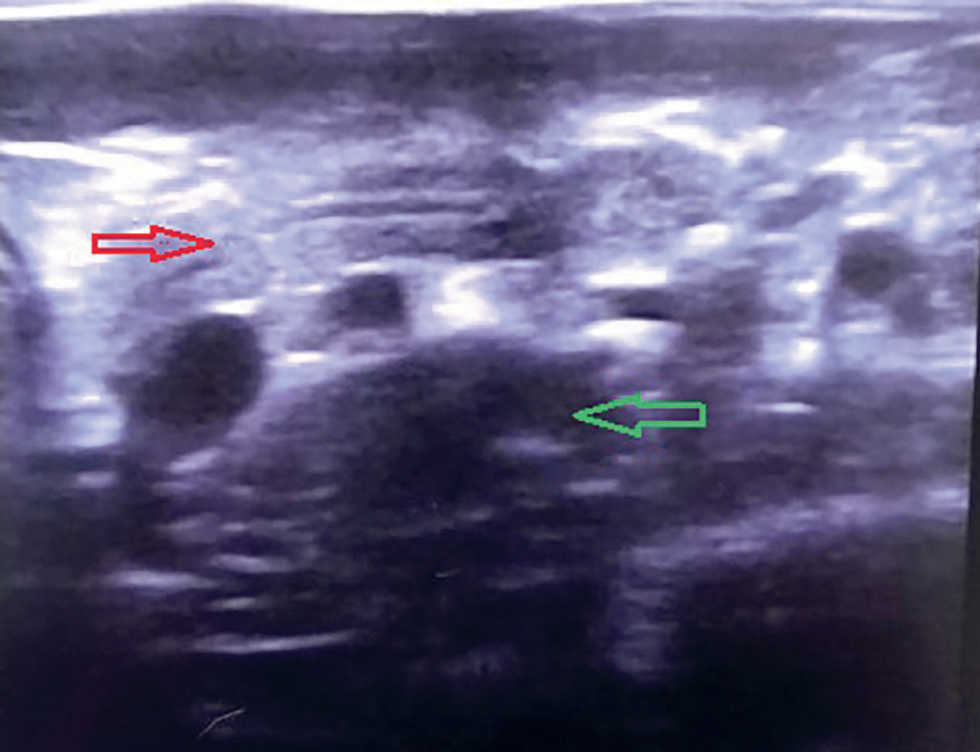

Лимфома у кошек что это 112 фото